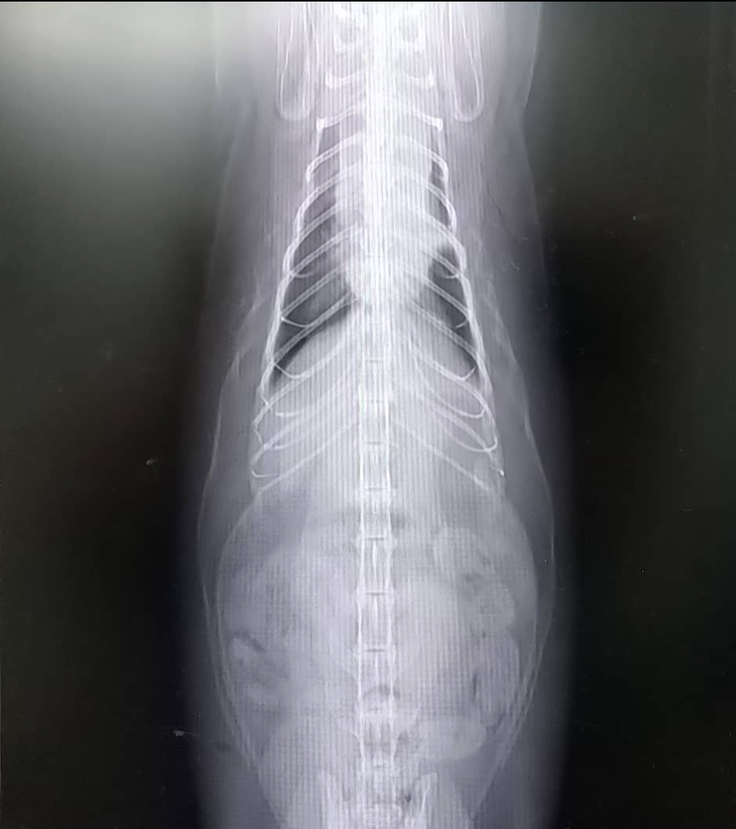

昨年てんかんを起こして以来、リンパ腫疑いのなか、クリニック独自の治療をしておりました。が、今年の7月に突然心臓発作のような状態になり、掛かり付けクリニックにて、血液検査、レントゲンを撮ったところ、レントゲンが真っ白で、胸水が貯まっており、抜く処置を行って頂きました

そのときのレントゲン写真と

と領収書を貼らせて頂きます

翌日、てんかんを起こすようになってから、クリニックと同時進行で診て頂いている医療センターにて詳細を検査して頂き、細胞診にて、猫白血病由来の悪性リンパ腫のなかでも悪性度の高い縦隔型リンパ腫と診断されました。